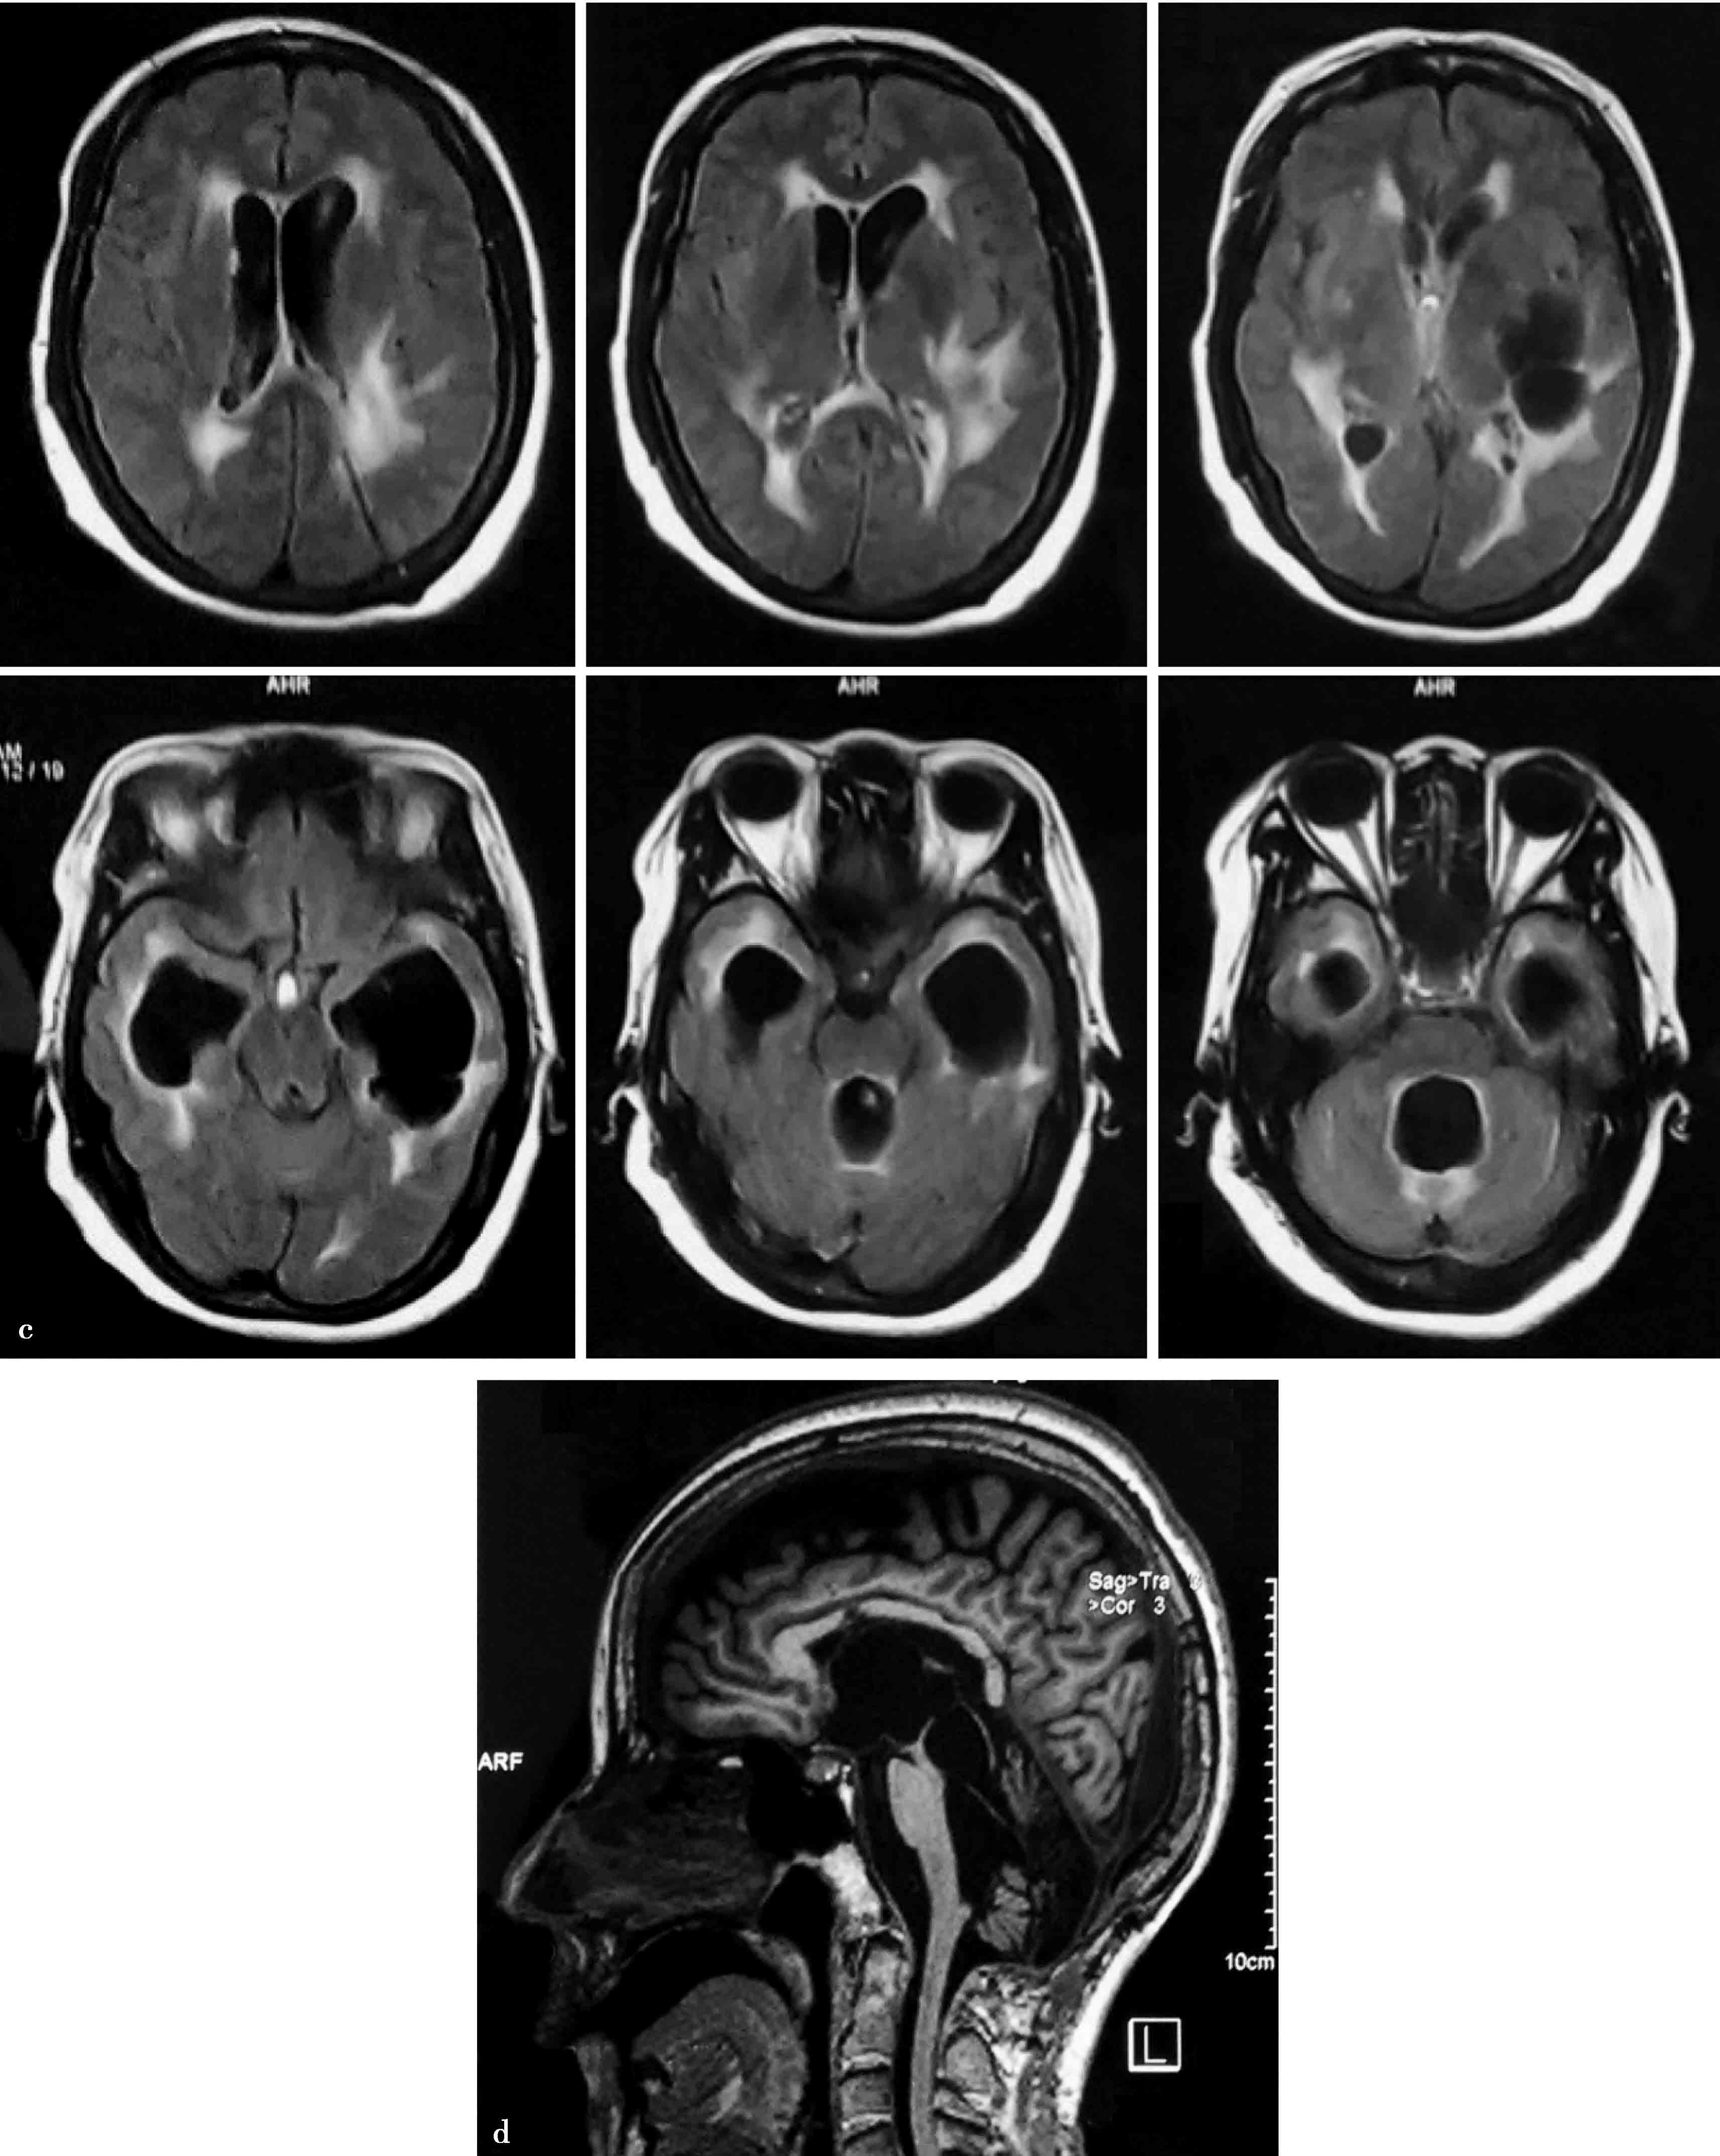

图3-1-4-7 孤立脑室

a.MRI显示孤立第三脑室;b.CT显示幕上脑室裂隙样,孤立第四脑室;c.双侧脑室分流术后,双侧脑室颞角孤立,第四脑室孤立;d.孤立第三脑室与孤立第四脑室同时存在